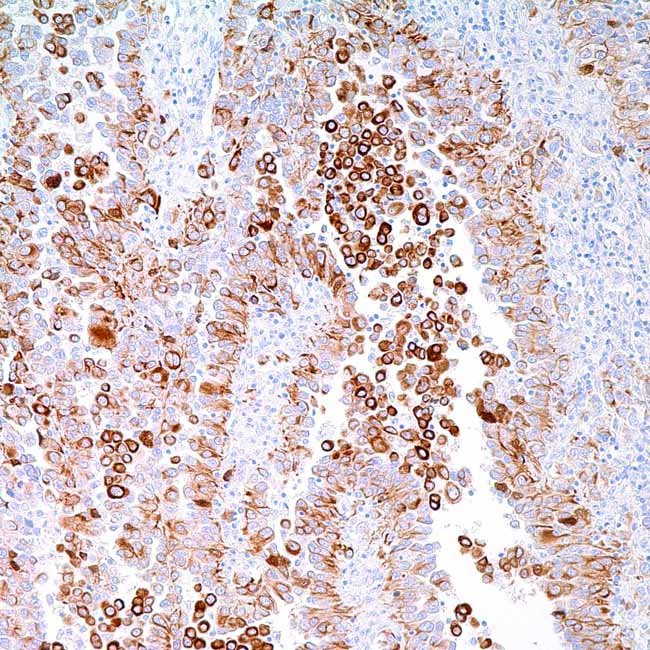

CK5 6 (D5 16B4)

The basic, high molecular weight cytokeratin 5 (58 kDa)is expressed in the superficial, intermediate, and basalcell layers of stratified epithelia, as well as in complexepithelia, transitional epithelia, mesothelial cells, andmesothelioma. Proliferating squamous epithelium alsoexpresses Cytokeratin 6 (56 kD), a high molecularweight, basic type cytokeratin that is frequentlycombined with Cytokeratin 16. Nearly all malignantmesotheliomas have positive cytokeratin 5 and 6antibody results, but lung adeno-carcinomas hardlyever do. Both squamous and undifferentiated large-cellcarcinomas have positive expression of CK 5 and 6. Lessthan 10% of prostate, colon, and breast cancers exhibitpositive staining for this antigen. Antibodies tocytokeratin 5 and 6 have also been effectively employedas a marker of myoepithelial cells in the prostate toidentify cancer.

VisualisationCytoplasmic

ControlMesothelioma